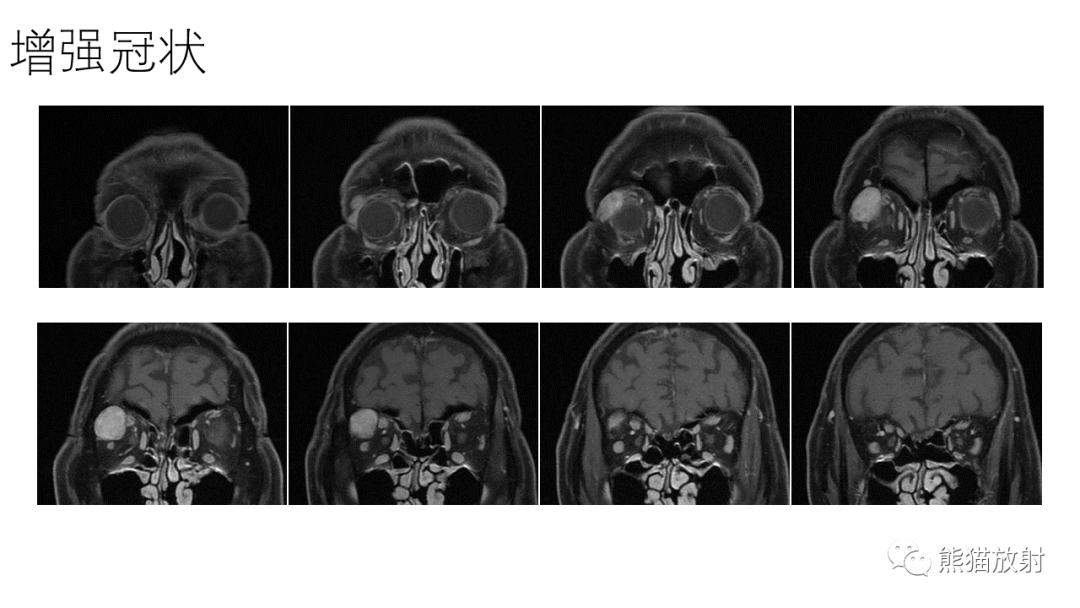

【PPT】泪腺多形性腺瘤 VS 眼眶淋巴瘤-3